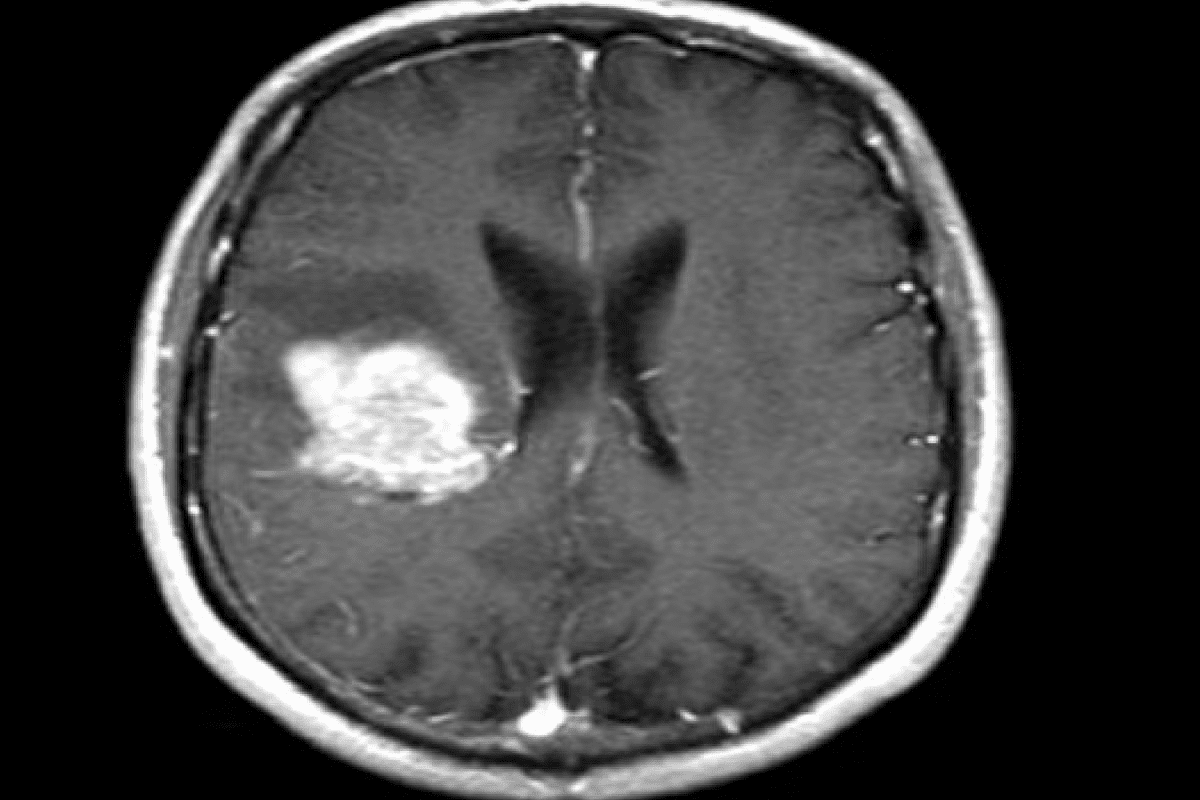

MRI and CT Scan Procedures

Magnetic Resonance Imaging (MRI) and Computed Tomography (CT) scans are top choices for brain scans. MRI shows soft tissues well, great for finding brain lesions. CT scans are fast and good for seeing calcifications and bleeding.